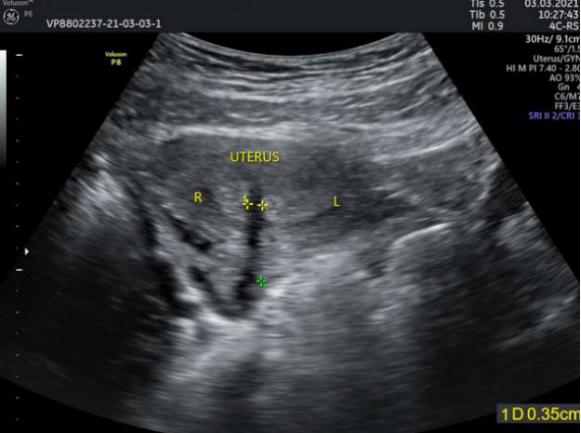

检查彩超结果显示:子宫形态轮廓大小正常。宫体中央见一低回声带,宽约11mm,将内膜分成两部分,并延续至宫颈外口。提示:子宫畸形,考虑完全纵膈子宫,双宫颈(双阴道?)。左侧宫颈管扩张,超声所见考虑经血潴留(左侧阴道闭锁?)。

术前彩超检查 子宫分为左右两个宫腔